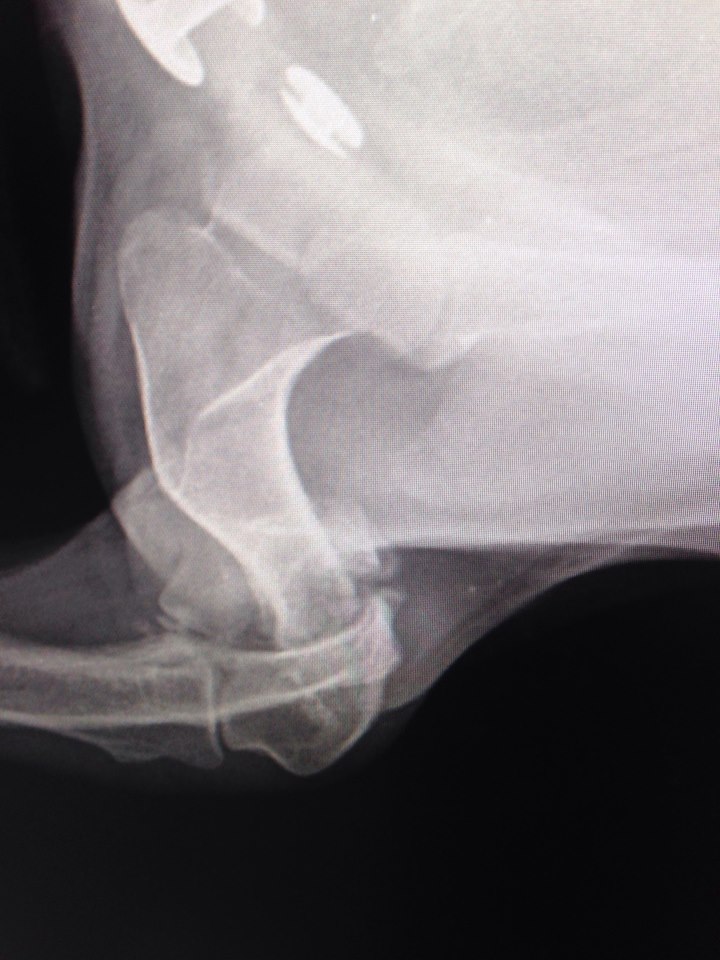

Вобщем все гораздо хуже оказалось.Только характер приятный,ласкавая.

Очень паршивый перелом.... сложная операция.

Не понятно куда и зачем одевали гипс.... зато стерилизовали.